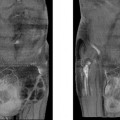

Hình chụp X-quang cho thấy lưỡi dao cắm rất sâu. Ảnh: AFP